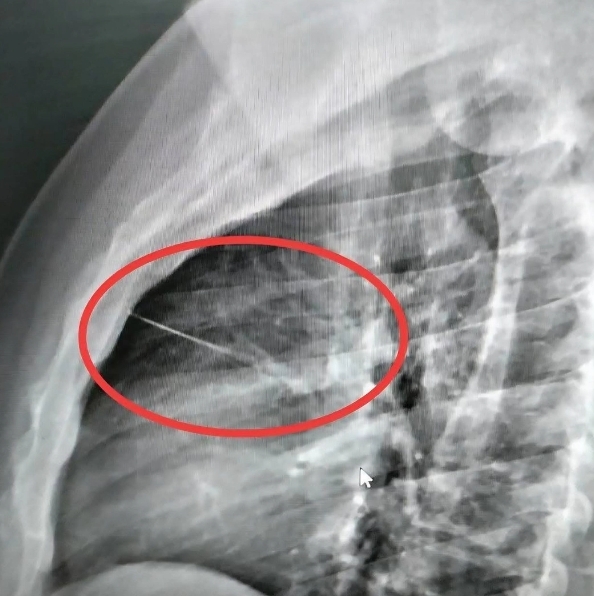

เมื่อไปถึงโรงพยาบาลอาการของนายบุญเลิศ ก็ยังไม่ดีขึ้น หมอจึงนำตัวไปเอกซ์เรย์ ปรากฏว่ามีวัตถุคล้ายของมีคมขนาดเล็กความยาวประมาณ 7 ซม.ทราบต่อมาว่าเป็นเข็มเย็บผ้าฝังอยู่บริเวณหน้าอกซ้ายใกล้กับหัวใจ แพทย์จึงส่งตัวไปผ่าตัดที่โรงพยาบาลศูนย์บุรีรัมย์ เพราะเป็นจุดอันตราย